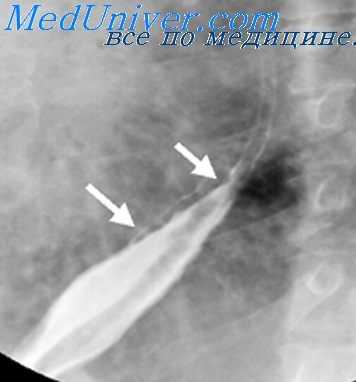

Деструкция стенки пищевода, вызванная эрозивным (коррозивным) или язвенным процессом, при рентгенологическом исследовании проявляется прямым симптомом — депо бария или нишей. Язвенная ниша имеет конусовидную или неправильную форму. Длинник ее расположен перпендикулярно контуру пищевода, размер колеблется от 0,2—0,3 до 0,6—0,8 см.

В краеобразующем положении она выступает за пределы внутреннего контура пищевода. При этом воспалительный вал у ее основания иногда обусловливает своеобразную краевую деформацию стенки пищевода, имеющую вид цифры 3. Хроническое течение воспалительно-деструктивного процесса в пищеводе сопровождается конвергенцией складок слизистой оболочки к нише, эзофагитом, сужением и деформацией (укорочением) органа.

Изъязвления пищевода часто (до 50%) сочетаются с аналогичным процессом в желудке или двенадцатиперстной кишке, а также с грыжами пищеводного отверстия диафрагмы. Язвенную нишу пищевода необходимо дифференцировать от скопления (депо) бария в кратере распадающейся опухоли, в небольшом дивертикуле и деформированных или изъязвленных участках стенки, появившихся на почве бывшего ожога, инородного тела, периэзофагита или варикозного расширения вен.

В распознавании изъязвлений, возникших вследствие инородных тел или ожога пищевода, большое значение имеют данные анамнеза, а язв при варикозном расширении вен — наличие типичной для основного заболевания рентгенологической картины. В отличие от распадающейся опухоли пептическая язва пищевода имеет более правильную форму и ровные очертания.

Инфильтративный вал у ее основания симметричен, глубина кратера превышает его ширину, а степень сужения просвета пищевода в зоне поражения в процессе исследования меняется в широких пределах, особенно при применении спазмолитических препаратов. Подобной изменчивости рентгенологической картины при раковом поражении пищевода не наблюдается. Однако в ряде случаев отличить рентгенологически пептическую язву пищевода от язвенной формы рака не представляется возможным [Петерсон Б. Е., 1969].